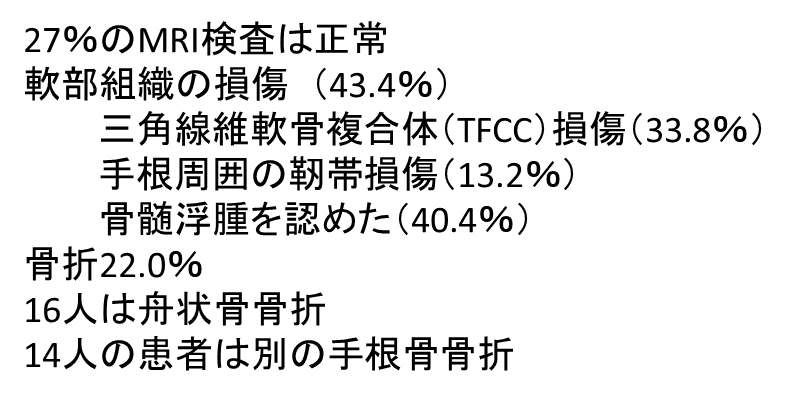

137症例のうち骨折がみられたのは22%だった

それ以外は正常(27%)であり

43.4%が軟部組織損傷だった

私も最終的にはMRIならと期待していましたが

紹介した以外の文献以外は

圧倒的にMRI有用性を謡われてきました

他の文献が主戦場「ER」でした

この「整形外科より紹介」

この部分が

このような結果を導いていると思われます

こういうネガティブな要素もあるということだけ

抑えておいてください